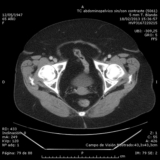

Desafío diagnóstico en urgencias: dolor abdominal ¿quirúrgico?

Introduccion El dolor abdominal agudo es uno de los cuadros urgentes de mayor desafío diagnóstico. La anamnesis, la exploración física minuciosa y las pruebas ...